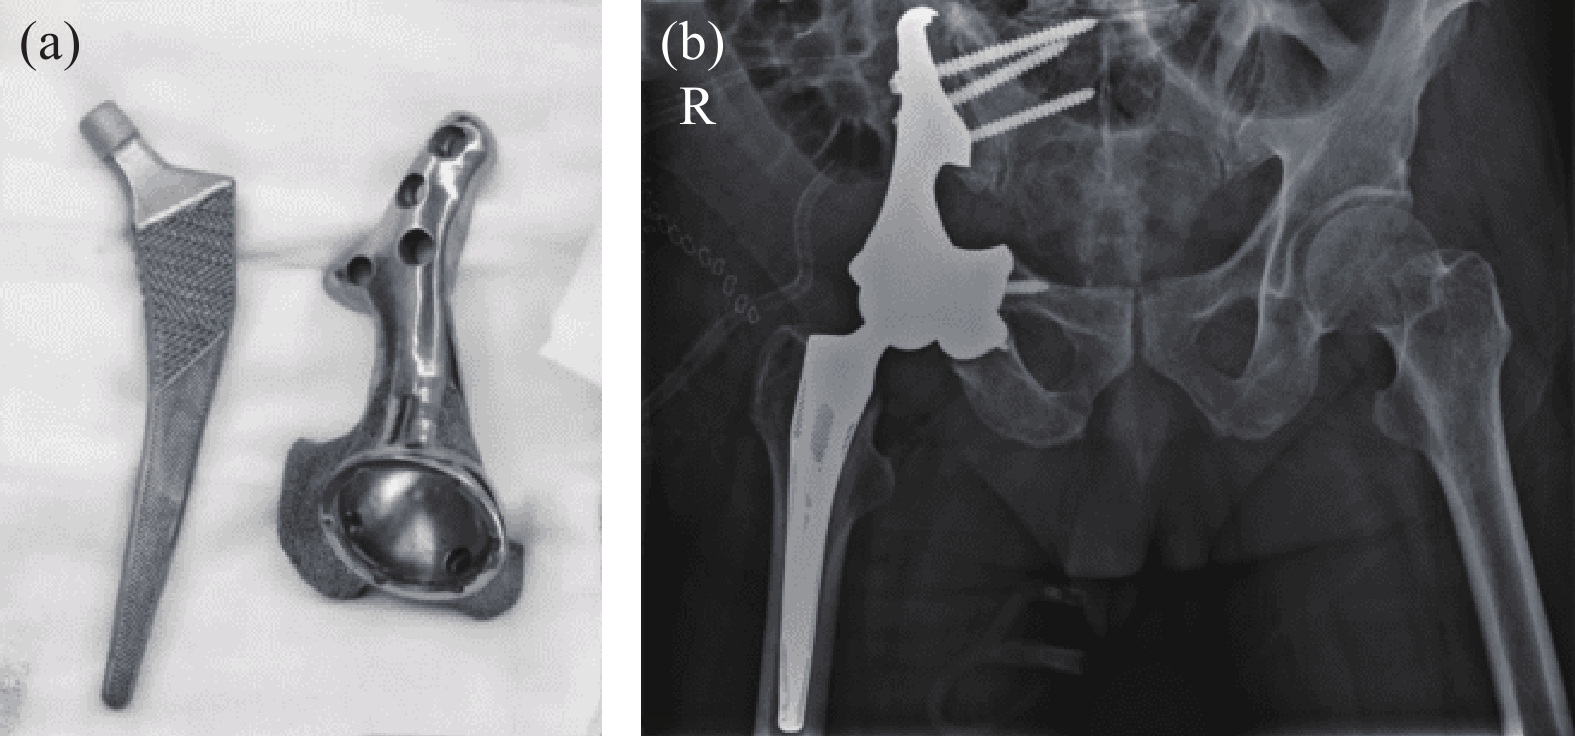

骨盆部位手术一直是骨科手术中的难题之一。2022年,大连大学附属中山医院为骨盆肿瘤导致右髋关节变形的患者进行了3D打印钽半骨盆及髋关节假体植入(图10(a)),进一步拓宽了3D打印多孔钽的应用[25]。该患者受损部位大,需要切除髂骨、髋臼及部分或全部耻骨和坐骨,切除及植入手术难度高。该院通过3D打印为患者定制的植入体与患者切除后缺损部位高度匹配(图10(b)),节省了植入手术时间。

图10 3D打印钽金属骨盆和髋关节:(a)打印成品;(b)植入人体后X光照片[25]